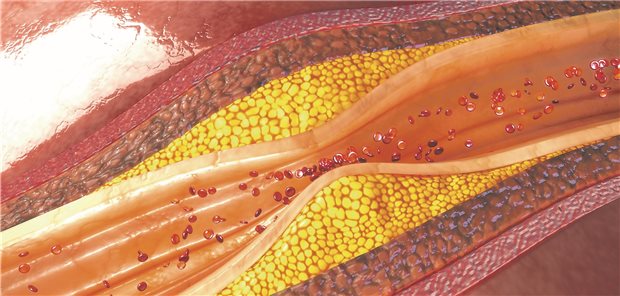

Forscher haben Veränderungen atherosklerotischer Plaques über Jahre hinweg dokumentiert. Eine Statintherapie verringert dabei wohl weniger die Progression als die Zusammensetzung der Läsionen.